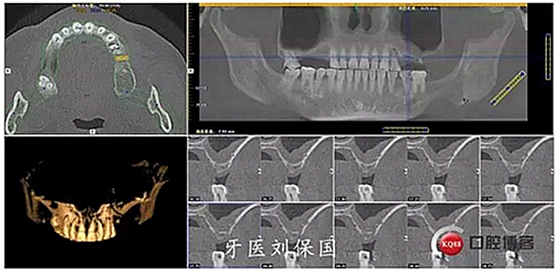

1.術(shù)前CT: